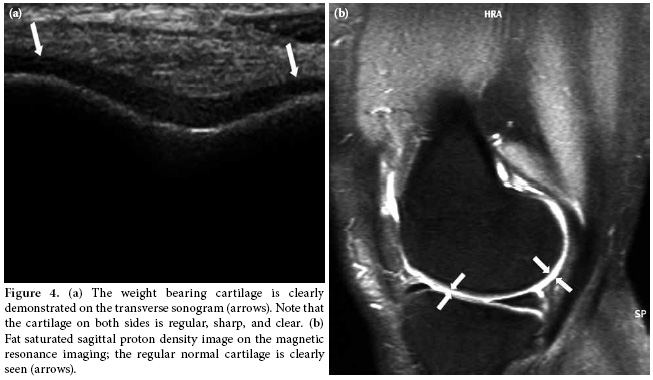

In the second position, the weight bearing medial and lateral femoral condylar cartilage thickness and clarity were evaluated with the knee in maximum flexion. The femoral condylar cartilage was measured on the weight-bearing area approximately 1.5 cm away from the intercondylar notch (Figure 3). The cartilage morphology was assessed using a scale: 1 for regular-clear (Figure 4a, b) and 0 for irregular, non-clear (Figure 5a, b). Finally, all the patients were evaluated for popliteal cysts with the knee extended in a prone position, and any presence of popliteal cysts was recorded.